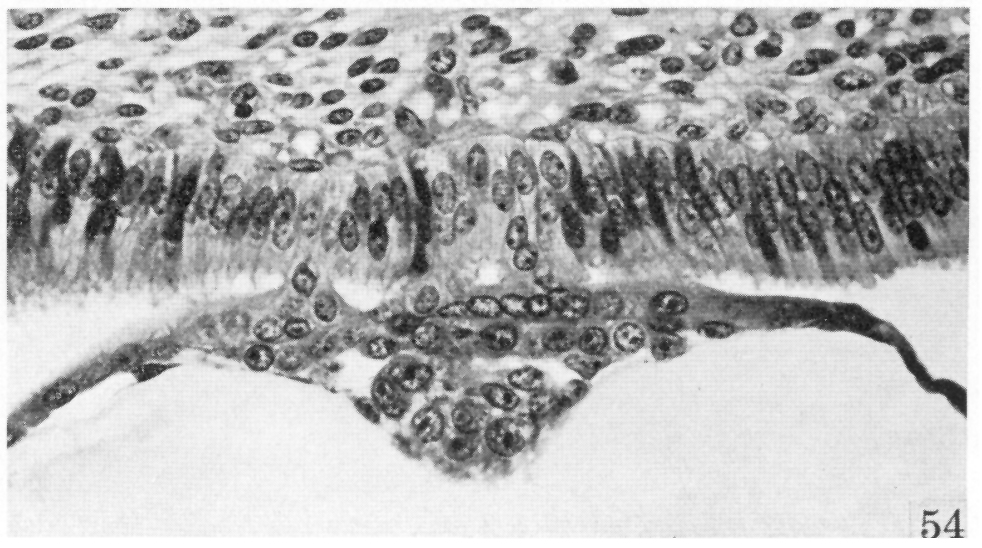

Fig. 54.

Heuser and Streeter, 1941